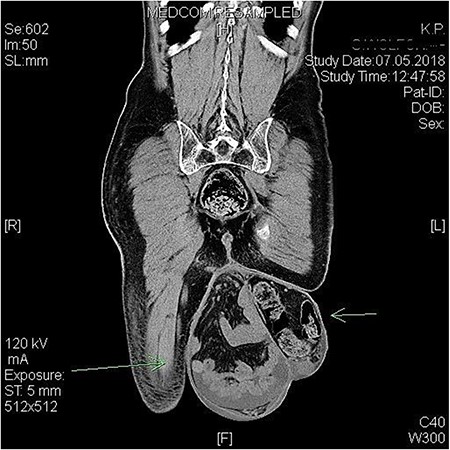

The CT scan of the abdomen disclosed a complete scrotal shift of both small intestine and sigmoid colon and a bilateral Grade II hydronephrosis (Fig. 1). The patient was then referred to our surgical department for the operative hernia repair.

Preoperative CT scan showing the bilateral giant scrotal hernia with massive shift of intestine into scrotum.